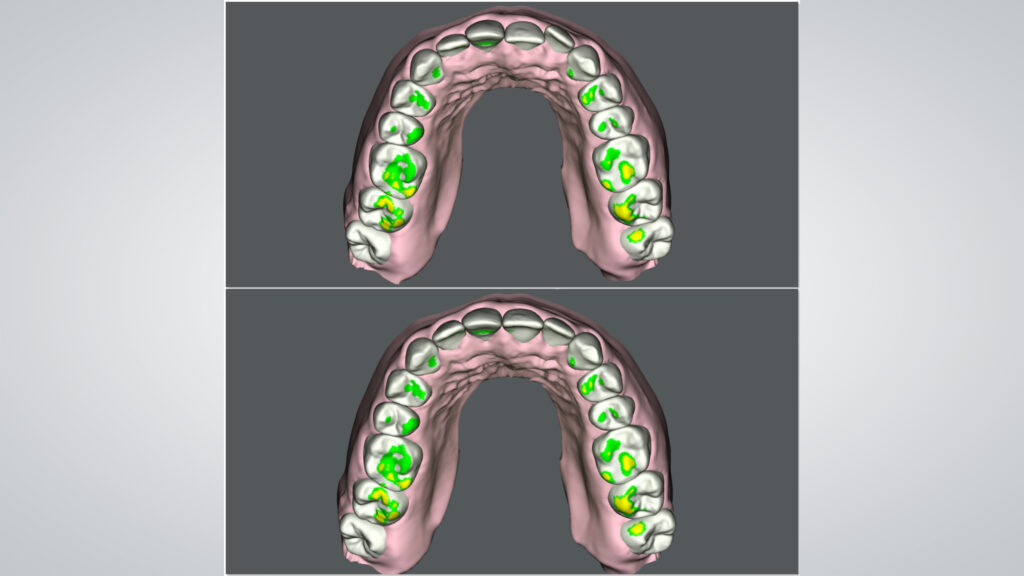

Im vorliegenden Fall wurde eine leichte extraorale Verschiebung der Mittellinie nach links festgestellt. Zudem zeigte die interkommisurale Linie eine Diskrepanz von links nach rechts. Bemerkenswert war die signifikante Volumendifferenz der rechten Lippenpartie im Vergleich zur linken. Zudem wurde eine Abweichung zwischen extraoraler und intraoraler Mittellinie identifiziert. Die klinische Befundung ergab einen Engstand im Oberkiefer, welcher als Rezidiv nach einer kieferorthopädischen Behandlung interpretiert wurde. Zusätzlich wurden ein Zahnschmelz-Chipping, eine Kunststoffverblendung am endodontisch vorbehandelten Zahn 11 sowie ein mild ausgeprägtes Gummy Smile diagnostiziert; insgesamt zunächst ein vergleichsweise einfacher Fall für ein Aligner-Bleaching-Veneers-Konzept. Aber: Obwohl der Fall auf den ersten Blick wie ein einfacher „Kandidat“ für ein Aligner-Bleaching-Veneers-Konzept wirkte, offenbarte eine detaillierte Untersuchung des Unterkiefers die volle Komplexität. Die Unterkieferfront zeigte eine blockartige Verschiebung. Während die rechte Seite intrudiert und nach bukkal protrudiert war, zeigte die linke Seite eine Extrusion und Retrusion (Abb. 4). Diese spezifische Konstellation erklärte die in der ästhetischen Analyse festgestellte Lippenposition. Ursache für die Situation war ein fehlerhaft positionierter Retainer. Der Retainer am rechten Eckzahn war vor Jahren abgebrochen. Das verursachte diese negative Entwicklung bei einer ansonsten positiven Retainer-Funktion. Die Blockbewegung des Unterkiefers musste auf diesen Umstand zurückgeführt werden.

Bevor wir mit der Planung der Behandlung beginnen konnten, benötigten wir einen detaillierten Fotostatus, eine Panorama-Röntgenaufnahme sowie einen digitalen Scan des Gebisses. Es war klar, dass eine initiale Korrektur mittels Alignern erfolgen musste, um den Okklusionsplan im Bereich der Frontzähne zu regulieren (Abb. 5 und 6). Die zeitliche Begrenzung stellte hierbei eine echte Herausforderung dar, denn das Zeitfenster ermöglichte nur zehn Aligner-Schienen pro Kiefer (SureSmile Aligner, Dentsply Sirona). Nach Anwendung der siebten Schiene, einem Zwischenscanning und der Modellherstellung war es für das zahntechnische Team an der Zeit, aktiv zu werden.